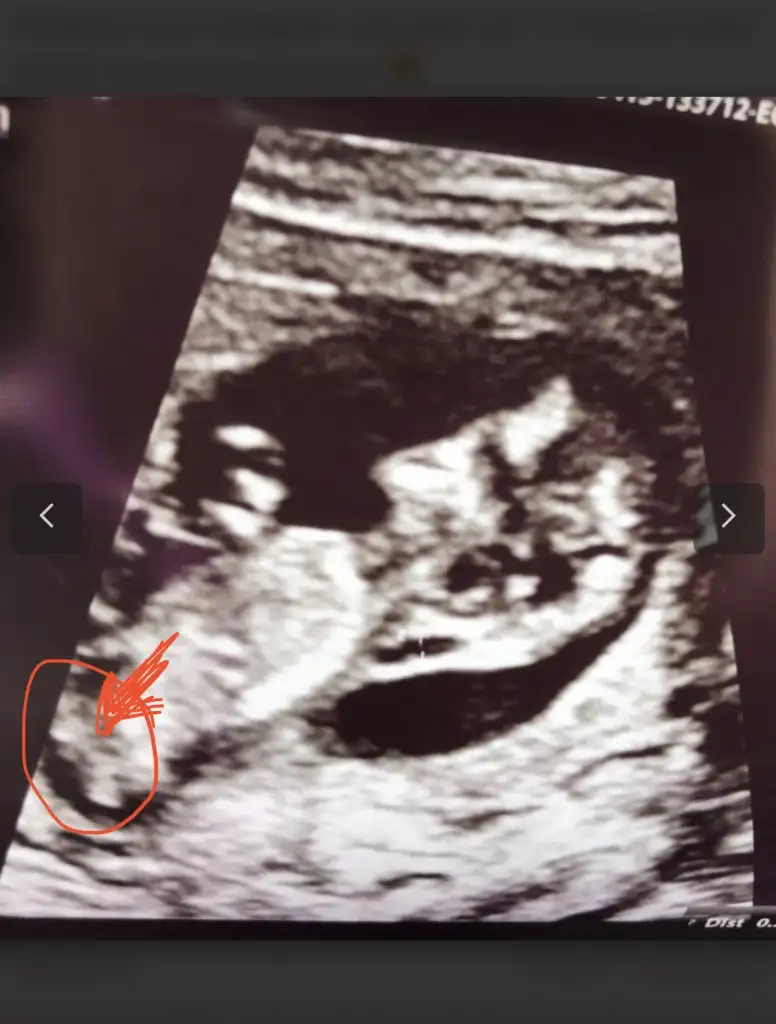

Bu bebiş daha boyluSağol canım cümlemiziElimde öyle duruyor kendime dönderince sol oluyor hepsi ama kafama başka bişey takıldı 8+2 de gittim mm 21 yazıyor büyük oğlumda 9. Haftada 20 mm miş doğum 2 gün erken gözüküyor allahım nelerle uğraşıyorum